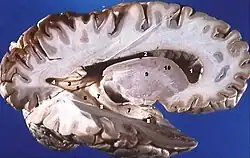

Aus dem unpaaren Hirnbläschen des Endhirns entwickelt sich ein Paar ungefähr halbkugelförmiger Gebilde, die Hemisphärenbläschen, die je zur Großhirnhemisphäre (Hemisphaerium cerebri) einer Seite werden. Neben der unpaaren medianen Gewebebrücke (Lamina terminalis) entstehen beide Hemisphären miteinander verbindende Querbahnen, die Kommissursysteme des Endhirns wie der breite Balken (Corpus callosum). Linke und rechte Hemisphäre werden durch eine tiefe Längsfurche (Fissura longitudinalis cerebri) geschieden und umschließen je einen Seitenventrikel als inneren Liquorraum. Jede der Hemisphären enthält innen gelegene Kerngebiete als Basalganglien (Nuclei basales), die aus dem ventralen (bauchseitigen) Telencephalon entstehen. Diese werden umhüllt vom außen liegenden Hirnmantel (Pallium), der aus dem dorsalen (rückenseitigen) Telencephalon hervorgeht.

Die Oberfläche des Palliums besteht als Rinde des Endhirns oder Großhirnrinde (Cortex cerebri) – ähnlich wie die Kleinhirnrinde (Cortex cerebelli) – aus Grauer Substanz mit Nervenzellkörpern in mehreren Schichten. Darunter liegt als sogenanntes Marklager aus Weißer Substanz ein dichtes Geflecht von Nervenfasern, deren Nervenzellfortsätze vielfältige Verbindungen schaffen. Als Assoziationsfasern verbinden sie unterschiedliche Areale des Cortex cerebri der Hemisphäre gleicher Seite untereinander, als Kommissurfasern mit solchen der Gegenseite und als Fasern von Projektionsbahnen stellen sie auf- oder absteigend Verbindungen von und zu verschiedenen anderen Regionen des Gehirns bzw. des zentralen Nervensystems dar.

Die aus dem ventralen Telencephalon hervorgehenden subkortikalen Kerne werden auch als basale Kerne oder Nuclei basales bezeichnet bzw. als Basalganglien. Sie liegen an der Basis des Endhirns seitlich und bauchseitig eines Seitenventrikels und schließen an Bereiche des Thalamus des Zwischenhirns. Infolge der hindurchziehenden Fasern von und zur Großhirnrinde hat ein Teil der Kerne ein gestreiftes Aussehen, weshalb diese auch als Corpus striatum (Streifenkörper) bezeichnet werden.